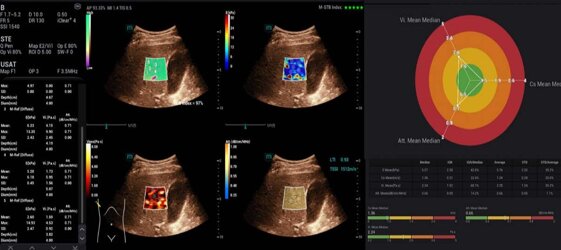

STVi consente la valutazione quantitativa della viscosità dei tessuti e fornisce immagini multiparametriche in tempo reale, offrendo un approccio più completo alla diagnosi per immagini e all'analisi quantitativa di malattie epatiche croniche, lesioni mammarie e altre condizioni.

M Reference è uno strumento di analisi combinata multiparametrica che consente diagnosi MPUS in tempo reale, nella stessa sezione e nella stessa schermata. A differenza delle tradizionali immagini ecografiche singole, offre informazioni diagnostiche multidimensionali e indicatori di valutazione quantitativa per le malattie.